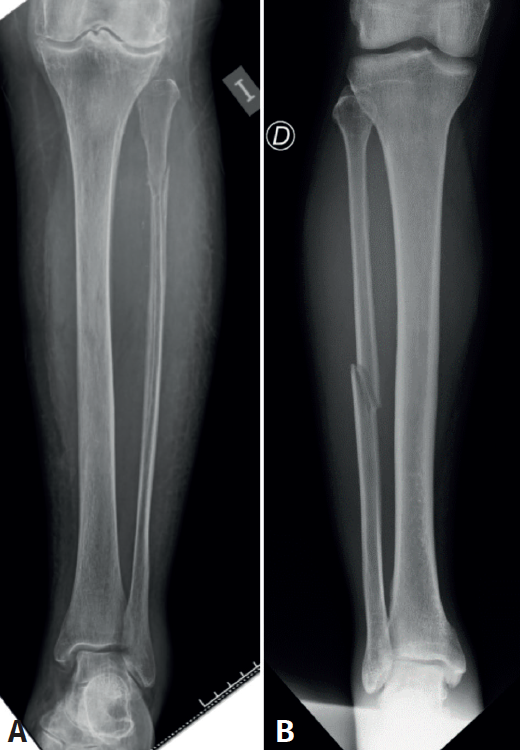

Desde el punto de vista epidemiológico, dividimos la muestra en fracturas Weber C diafisarias y fracturas de Maisonneuve (fracturas de la cabeza de la fíbula o subcapitales según Michal Tuček et al.)(5)(Figura 1).

En cuanto al tipo de fractura fibular, 10 (52,6%) fueron diafisarias y 9 (47,4%) de Maisonneuve. Un total de 9 pacientes presentaban fracturas del lado derecho y 10 del izquierdo.